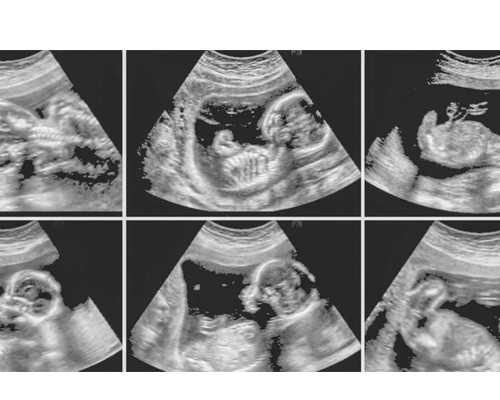

大家想做三代试管婴儿的话,首先得由试管医生评估决定您是否需要做试管婴儿,因为试管婴儿技术有自己的适应症。确定大家能做试管婴儿之后,医生会要求夫妻双方去做个试管婴儿前的化验检查,检查结果出来若无异常指标就可以做试管,不过这个阶段会花费5000-10000元左右的检查费用;然后就是进入促排阶段,促排卵一段时间后,女性要进行B超监测卵泡的发育情况。卵泡发育达标后,医生会给女性注射夜针(hcg),这之后的34-48小时内安排女性取卵,男性同步取精。这个阶段的费用大概是在1-2万元左右;取出的精子和卵子会被送到实验室进行体外受精,受精后的一段时间会培育成胚胎。培育出来的胚胎会择优移植给女性,女性在移植14天后抽血化验,看看是否有成功怀孕。这个阶段的费用大概是主要2-3万元左右。苏州借卵子生子医院以上就是关于在苏州市立医院做第三代试管技术的费用,费用大概是在3-6万元左右。不过每个患者的实际情况是不一样的,所以在费用方面肯定是会存在差异的。